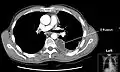

Chest computed tomography is more accurate for diagnosis and may be obtained to better characterize the presence, size, and characteristics of a pleural effusion. Lung ultrasound, nearly as accurate as CT and more accurate than chest X-ray, is increasingly being used at the point of care to diagnose pleural effusions, with the advantage that it is a safe, dynamic, and repeatable imaging modality.[15] To increase diagnostic accuracy of detection of pleural effusion sonographically, markers such as boomerang and VIP signs can be utilized.[16]